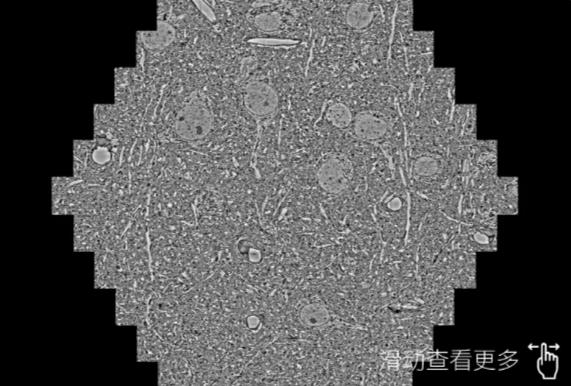

鼠脑切片。左图使用平谷蔡司平谷扫描电镜MultiSEM706对165μmx143pm面积区域成像,耗时仅需1.5秒。右图为鼠脑切片中30μm区域放大效果。样品由芝加哥大学B.Kasthuri提供。

使用蔡司高速平谷扫描电镜MultiSEM对1mm²人脑皮层组织进行高分辨成像,并对其中的各种细胞结构进行三维重构分析。左图展示了2x3mm²组织平面中锥体神经元的三维重构效果。右图显示了局部体积神经元三维重构。图像由哈佛大学chtman实验室提供,渲染图由D. Berger 制作。